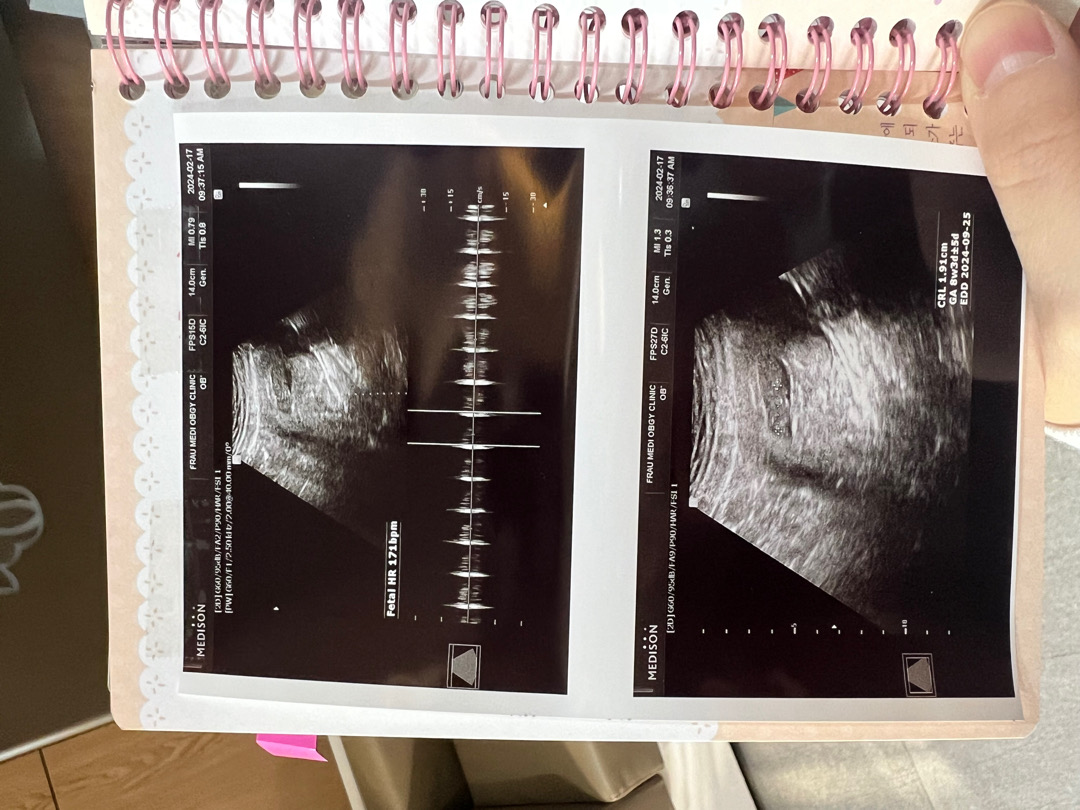

8w5d인데 배초음파

ㅠㅠ 애가 잘크고 있고, 심장소리도 정상이고 좋다고 하는데… 저희눈에는 잘 확인이 안되네요~~ㅠㅠ 질초음파로 하면 더 잘 보였을까요?! 젤리곰 기대했는데 ㅠㅠ

저 정도 안 보이면 다시 질초음파로 해주셨을 법도 한데 의사쌤 센스가🥲 저도 8주찬데 처음에 배 초음파 하려다가 근종에 가려 잘 안 보인다고 질 초음파 하니 2등신 애기 선명하게 보였어요~ 어쨌든 의사쌤이 거짓말은 안 했을테니 젤리곰 모양으로 잘 있을거예요!

배 초음파는 정말 안보이네요ㅠㅠ 배 초음파는 배가 어느정도 볼록(?) 나와야 보인다고, 임신중후반쯤 한다고 했어요~! 저도 7-8주차 질내초음파로 젤리 확인했어요^^ 엄청 잘 보여요!